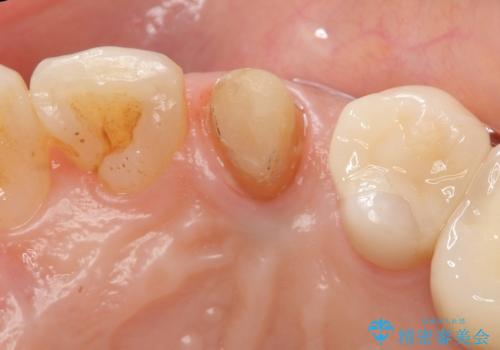

終了時

左:虫歯を除去したところ。遠心が歯ぐきより深い状態です。中:そのままかぶせようとすると、遠心が歯ぐきが腫れやすい状態です。右:エクストリュージョンをしたことで、遠心の歯ぐきの腫れが収まっていることがわかります。

術後は計画通り歯ぐきの腫れが収まり、炎症に強い歯ぐきになりました。

エクストリュージョンをしたことで、いくら歯磨きを頑張ってもどうしても腫れてしまう歯肉に対して、歯周囲組織の位置関係を変えることで根本的に解決しました。